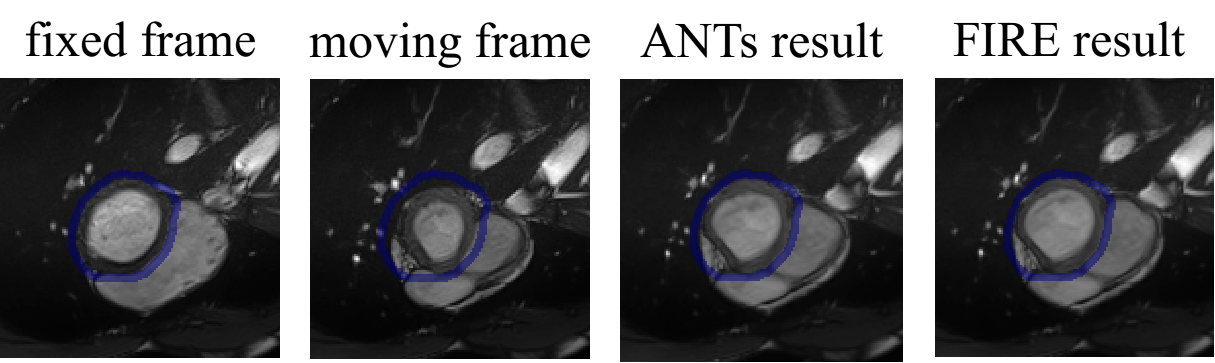

Table 2 and Fig. 6 show the results of the inter-modality registration performed on the ACDC data. The data only show small local displacement between frames thus both compared methods Dice scores over 0.9 on LVe. The Fire model achieved comparable performances with SyN.

Refer to caption

Figure 6: Representative results of registration on ACDC data. Outer contours of myocardium are shown in blue.